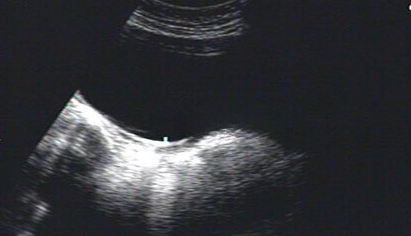

在试管婴儿促排卵治疗中,月经期进行阴道超声检查是制定个性化促排方案的关键步骤。这一特殊时机的选择,源于月经期女性生殖系统的独特生理状态,为医生提供了评估卵巢功能、排除病理干扰的黄金窗口。

一、月经期是卵巢储备功能的“真实底片”

月经第2-5天,卵巢处于基础状态,此时窦卵泡数量(AFC)的计数具有高度准确性。阴道超声可清晰显示直径2-9mm的窦卵泡,其数量直接反映卵巢储备功能。例如,35岁以下女性AFC正常值在15-20个,若低于5个则提示卵巢早衰风险。这一时期的超声图像不受药物干扰,能真实呈现卵巢原始状态,为后续促排卵药物剂量调整提供可靠依据。

现代阴道超声采用高频探头(5-9MHz),分辨率达毫米级,且无需憋尿,能清晰显示卵巢血流信号。医院严格遵循无菌操作规范,使用一次性探头套及耦合剂,感染风险极低。对于担忧疼痛的患者,可选择超细探头(直径1.8cm)并配合深呼吸放松,检查过程通常仅需3-5分钟。